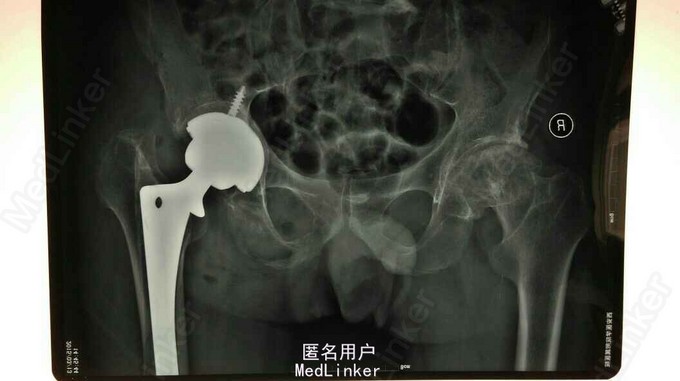

髋关节翻修

髋关节置换术后15年,疼痛2年。 15年前左股骨头坏死,在外院行股骨头置换术,2年前左下肢短缩,左髋关节疼痛,活动受限。

左下肢短缩4cm,左髋关节外展受限,叩痛阳性,左下肢血运,感觉正常。

左股骨头置换术后假体松动 完善术前检测后行髋关节翻修术,术中髋臼侧打压植骨,术后左下肢短缩1cm ,顺利出院。

年轻患者第一次置换还是应该全髋关节置换